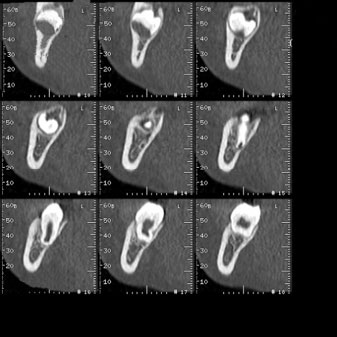

Tomografía computarizada Maxilar y Mandibular

Está indicado para el estudio implantológico, de extracciones dentales o valoración de patología en el hueso del maxilar superior e inferior.

Ejemplos